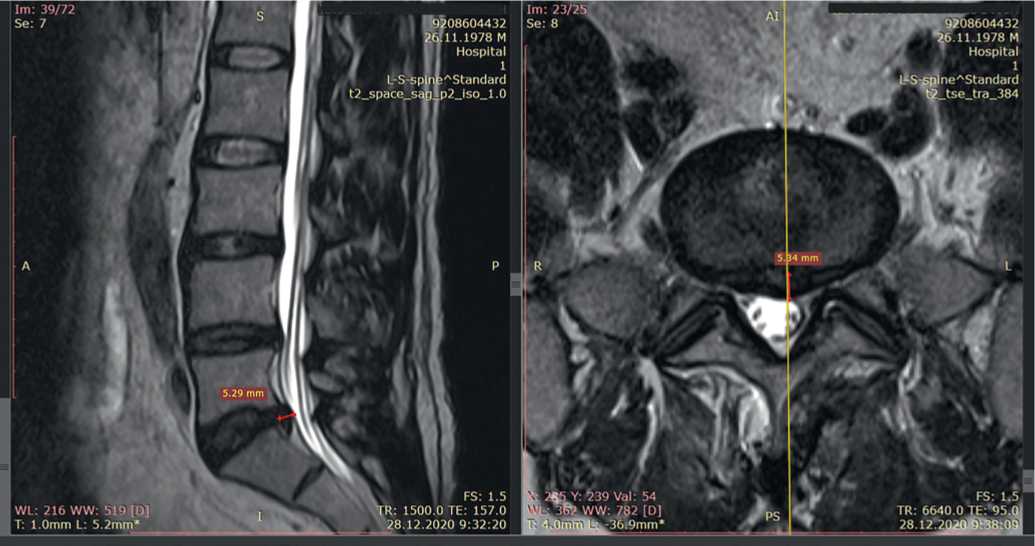

В дальнейшем пациент И. «для закрепления успеха» в течение 5 месяцев получал лечебные процедуры у кинезиотерапевта и остеопата, однако эффект получился обратным: вновь появились боли с тенденцией к интенсификации, пациент не мог стоять, сидеть и ходить. Трижды проведены анестезирующие блокады — без эффекта. При МРТ от 06.05.2021 выявлена парамедианная грыжа L5–S1 размером 7,8 мм (рис. 8).

Рис. 8. Магнитно-резонансная томограмма пациента И. при повторном обращении 06.05.2021: A) саггитальный срез, B) аксиальный срез на уровне межпозвонкового диска L5-S1, C) еще один саггитальный срез

Fig. 8. Magnetic resonance imaging of patient I. upon return visit on 05.06.2021: A) sagittal section, B) axial section at the level of the intervertebral disc L5-S1, C) another sagittal section

Повторно проведен курс акупунктуры в течение 3 месяцев. После лечения болевого синдрома и ограничений движений нет.

При катамнезе более чем через год на контрольной МРТ от 24.10.2022 отмечен регресс грыжи — визуализируется лишь протрузия 3,5 мм (рис. 9).

Рис. 9. Магнитно-резонансные томограммы пациента И. 24.10.2022: A) саггитальный срез, B) аксиальный срез на уровне межпозвонкового диска L5–S1

Fig. 9. Magnetic resonance imaging of patient I. on 10.24.2022: A) sagittal section, B) axial section at the level of the intervertebral disc L5–S1